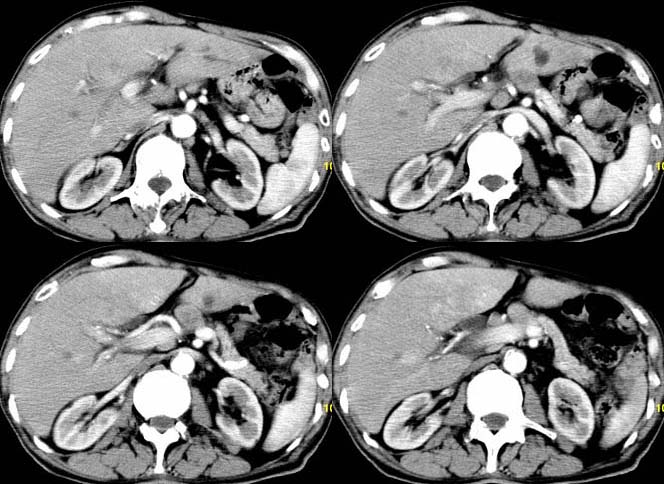

以下是引用余辉在2007-12-6 22:23:00的发言:[br]胆囊内多枚结石影,胆管全程扩张,右肝内病灶强化符合脓肿表现现(左肝病灶图像未传完),考虑急性梗阻性化脓性胆囊胆管炎合并肝多发脓肿(建议补传左肝病灶图像)